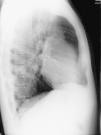

The patient denied smoking, alcoholic or drug habits and there was no history of previous admissions. Clinical evaluation of the patient revealed only discrete bronchospasm after pulmonary auscultation. A chest X-ray showed unilateral inferior rib notching of the 4–7th left ribs, inferior left lung hypotransparency and prominent vasculature (Figs. 1 and 2).

DiscussionClinical manifestations of the systemic-pulmonary arterial fistulae may be misinterpreted as patency of the ductus arterious or arterio-venous malformations and the symptoms depend, in part, on the functional repercussion that is proportional to the vessel size involved in the abnormal vascular anastomosis and heart distance.2,8 Chest X-ray in this type of vascular malformations demonstrates unilateral inferior rib notching and lung hypotransparency, suggesting pulmonary infiltrates and/or increased blood vessels (as in our case report).3